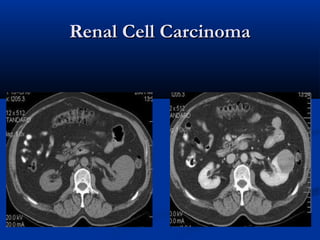

Renal Cell CarcinomaRenal Cell Carcinoma

before contrastbefore contrast

Contrast-enhanced dedicated renalContrast-enhanced dedicated renal

CT scanCT scan



CT scan obtained